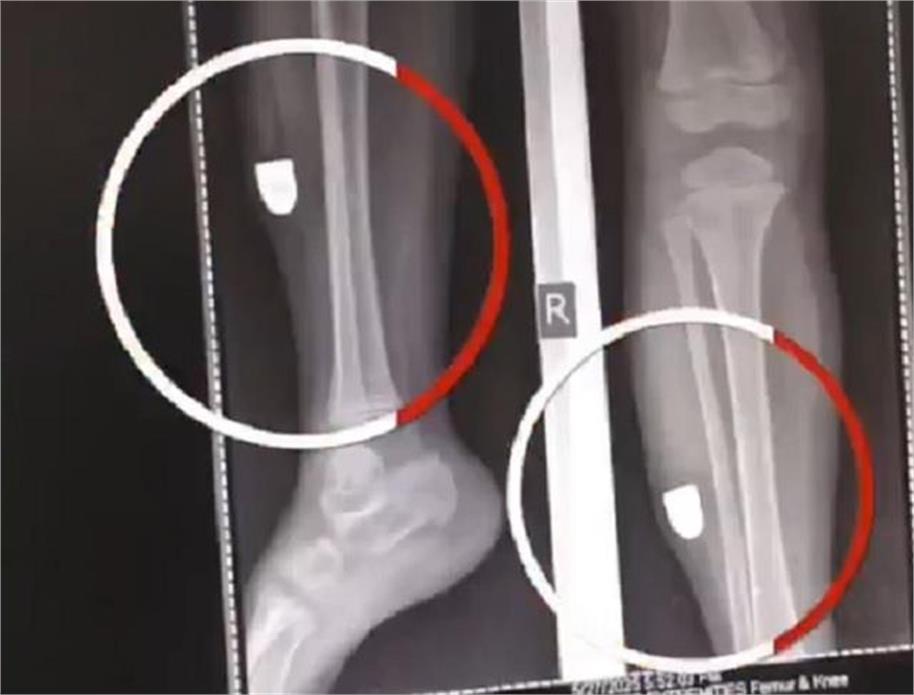

अमृतसर 28 मई 2025 : गेट हकीमां के पास स्थित फतेह सिंह कालोनी की रहने वाली साढ़े तीन वर्षीय मासूम बच्ची गोली लगने से घायल हो गई, जो अपने पिता के साथ ट्यूशन जा रही थी, के अचानक उसके पांव में गोली लगी और घायल हो गई। घायल होने के बाद उसका पत्थर समझ कर इलाज चलता रहा, मगर 4 घंटे पिता अपनी बेटी को लेकर डाक्टरों के पास घूमता रहा। जब उसे एक प्राइवेट अस्पताल में ले जाया गया तो एक्सरे करवाने पर गोली का पता चला। आप्रेशन के बाद उसके पांव से गोली निकाली गई और उसकी हालत स्थिर बताई जा रही है। घटना की जानकारी मिलने के बाद पुलिस हरकत में आई और अस्पताल में बयान लेने पहुंची और पिता के बयान दर्ज किए गए।

बच्ची के पिता आकाश का कहना है कि वह सोमवार शाम अपनी बेटी को ट्यूशन छोड़ने के लिए जा रहा था कि रास्ते में अचानक उसके पांव से खून बहने लगा। उन्हें जब कुछ पता न चला तो वह उसे घर ले गए उसकी मरहम पट्टी करवाई मगर उसकी बेटी दर्द से कराह रही थी, जिसे निजी अस्पताल ले जाया गया, जहां एक्स-रे के बाद पता चला कि उसके पांव में गोली लगी है और उसे आप्रेशन के बाद निकाला गया। लोगों का कहना है कि यह स्थानीय कानून व्यवस्था और लोगों में कानून के प्रति भय के अभाव का ही अभिप्राय हो सकता है कि गोलियां, बम्ब चलना आम बात हो रही है।